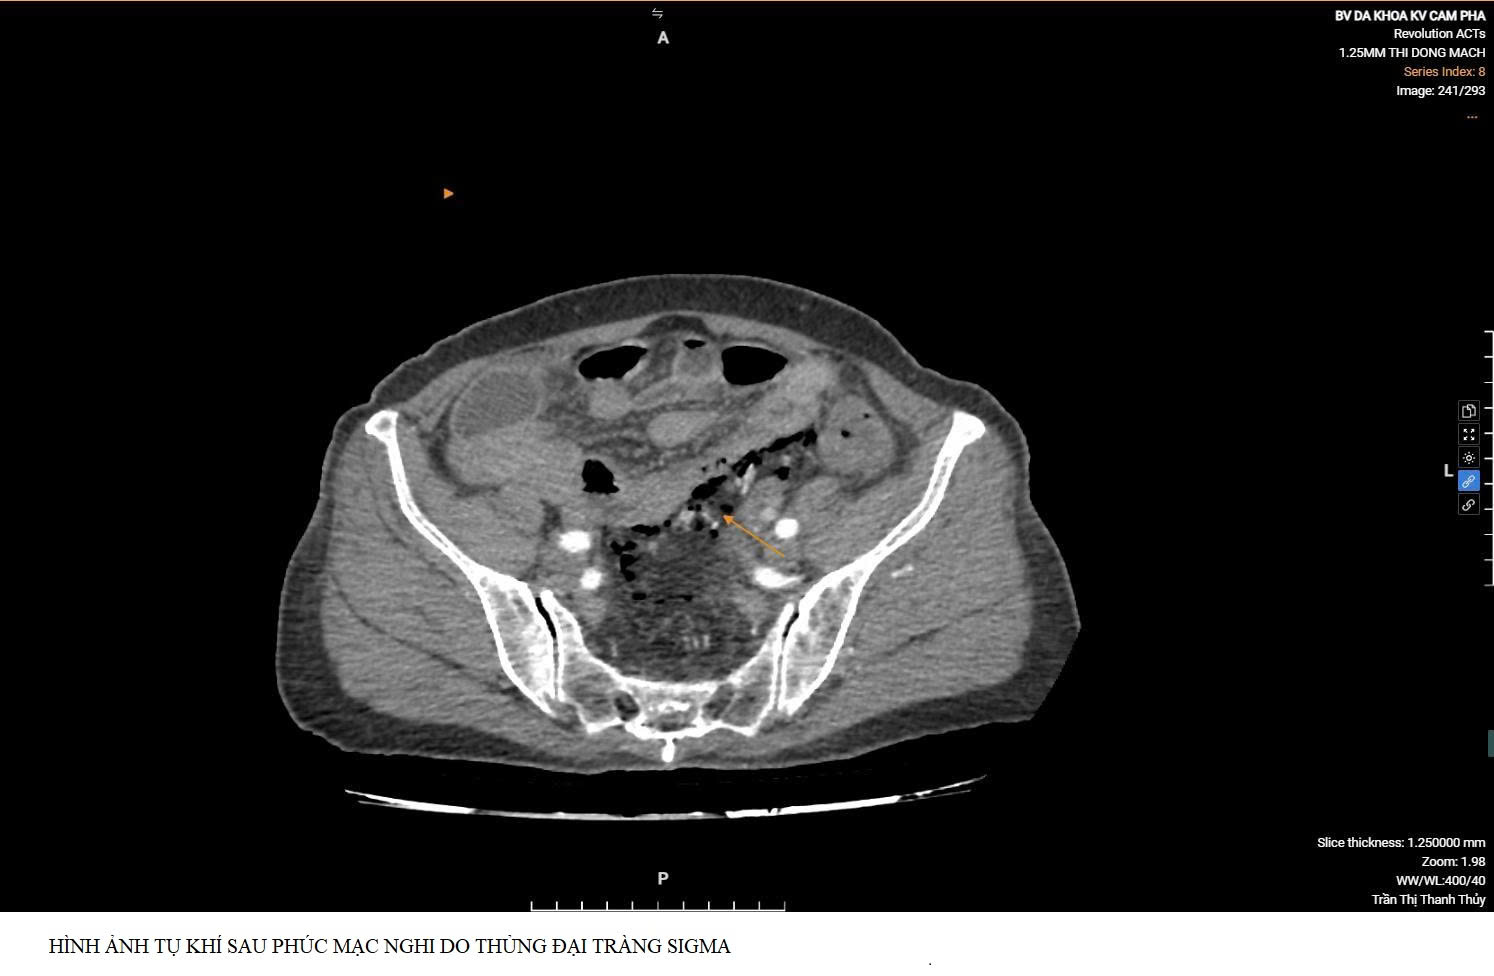

Nhận định đây có thể là một bệnh lý ổ bụng tiềm ẩn diễn biến nặng, bệnh nhân được chỉ định chụp cắt lớp vi tính ổ bụng cấp cứu. Kết quả ghi nhận: Hình ảnh tụ khí sau phúc mạc - dấu hiệu gợi ý thủng đại tràng sigma. Đây là một dấu hiệu kín đáo trên lâm sàng nhưng rất có giá trị trong chẩn đoán, giúp định hướng kịp thời xử trí tiếp theo.